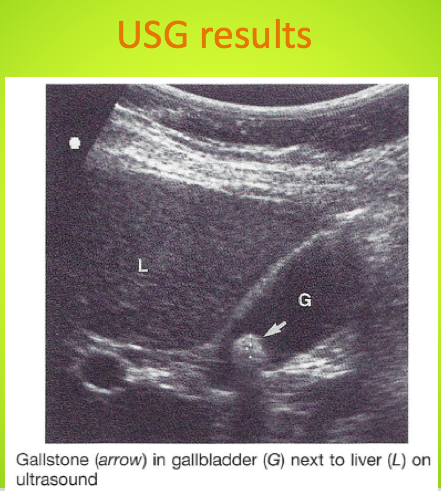

What is the test of choice for biliary colic?

Ultrasonography (–Sn 89%, Sp 97%, LR+ 30, LR– 0.11)